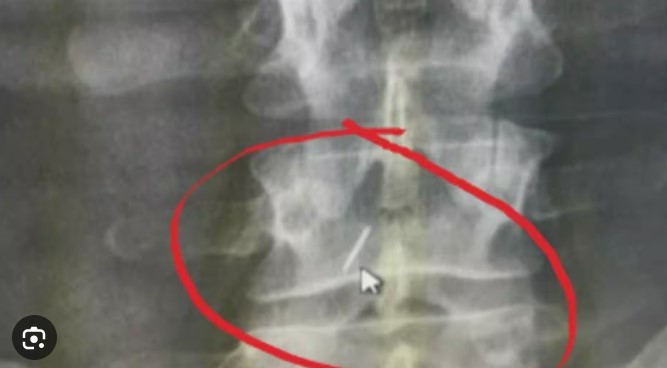

बेंगलुरु: सर्जरी के दौरान रीढ़ में छोड़ी 2 इंच की सुई, दो साल बाद...